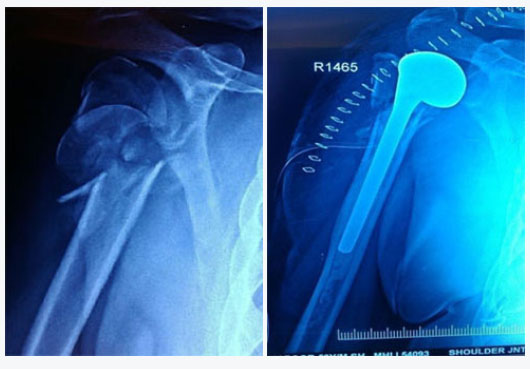

Shoulder replacement surgery is most commonly used for severe degenerative joint disease (osteoarthritis) or rheumatoid arthritis of the ball-and-socket joint. When the smooth surfaces (cartilage) of the ball and socket become rough, they rub against each other rather than glide. This rubbing causes pain and stiffness that limits daily activities, as well as interferes with sleep. Other indications that justifies shoulder replacement are severely communited fracture of proximal humerus which cannot be reconstructed and avascular necrosis of humeral head. A shoulder replacement is performed to alleviate shoulder pain. It also helps to improve the range of motion of your shoulder joint, which also improves your function and the quality of your life.

Here, the ball (humeral head) of the shoulder joint is replaced with an implant that includes a stem with a smooth, rounded metal head. The socket (glenoid) is replaced with a smooth, specialized plastic that is cemented into place.

Where only the ball (humeral head) is replaced with metal stem and head.

Shoulder replacement is performed in the hospital with the help of an experienced, specialized surgical team. The procedure generally takes 2 hours. Afterwards patients stay in the hospital for 3-4 days. To get to the shoulder joint an incision is made on the front of your shoulder. After exposing the shoulder joint, the damaged ends of the bone (humerus and glenoid) are removed. The bone is prepared for the replacement with the artificial joint. The artificial joint is made of metal, usually a titanium or a cobalt-chrome alloy. For a standard shoulder replacement the stem is placed inside the humerus bone. The glenoid component is made of a special plastic (polyethylene). The glenoid is cemented into place. Not all patients require a glenoid component and the final decision to use a glenoid component is made during the surgery. For reverse shoulder replacements the ball is secured to the socket with a press-fit and supplemented with screws. The humeral stem is then press-fit or cemented into place. A high-strength plastic then is placed to act as a spacer between the stem and the ball.